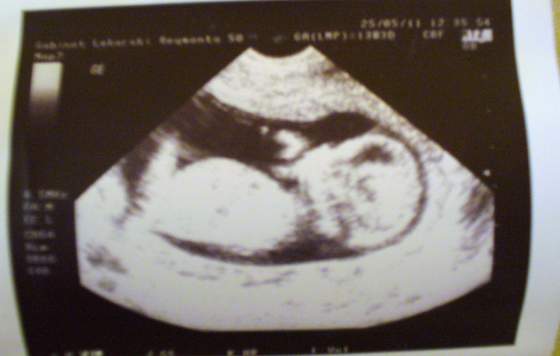

My dzisiaj cały dzień na działce u rodziców - ja odskoczyłam jedynie na wizytę u mojej ginki.:-) Nasza dzidzia ma już 68,30mm i rośnie jak na drożdżach, przybliżyła się do terminu wg OM -pokazywało na 29 listopada..bardzo ruchliwa jest nasza dzidzia i..ma długie nogi:-D..a tu foteczka;-)

Załączniki

• P1030602.jpg

P1030602.jpg

18,5 KB · Wyświetleń: 71